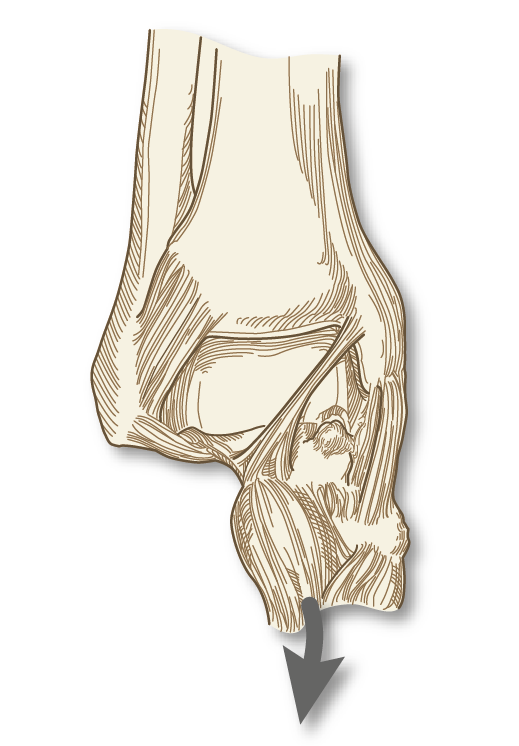

En comparación con los procesos de pinzamiento anterolateral y posterior, el pinzamiento de partes blandas en la zona medial se halla mucho menos recogido en la literatura (Figura 8). Así, se han descrito casos aislados después de una lesión del fascículo profundo del ligamento deltoides, después de una lesión por inversión que causa bandas cicatriciales en dicho fascículo profundo del ligamento deltoides y resultar comprimido entre la cara medial del astrágalo y el maléolo medial. Se han descrito también casos de dolor por pinzamiento del fascículo tibioastragalino anterior por traumatismo directo o por laxitud aumentada tras desgarro de los ligamentos tibioperoneos(1).

Figura 8. Pinzamiento del ligamento tibioastragalino anterior sobre la cúpula astragalina. Basado en: Ferkel RD (ed.). Foot and Ankle Arthroscopy. 2nd edition. Philadelphia; Wolters Kluwer; 2017.